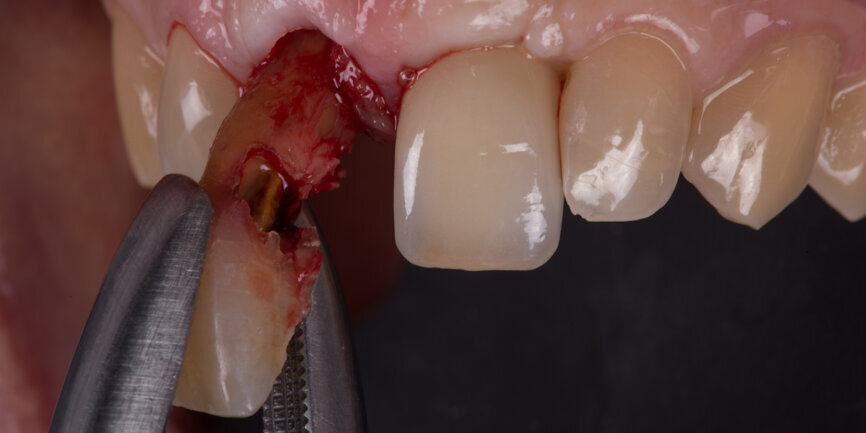

Tooth #11 was extracted atraumatically without raising a flap or performing an osteotomy (Fig. 4). The extraction socket was meticulously cleaned and rinsed with Betadine. The drilling sequence included 2.2, 2.8, 3.2 and 3.7 mm drills (Fig.5). The implant was placed with a final torque of 80 N cm (Figs. 6 & 7). In its final position, the implant platform lay 4 mm below the ideal gingival margin (at the same level of the adjacent implant platform; Fig.8).

Extraction and socket preservation of tooth #12